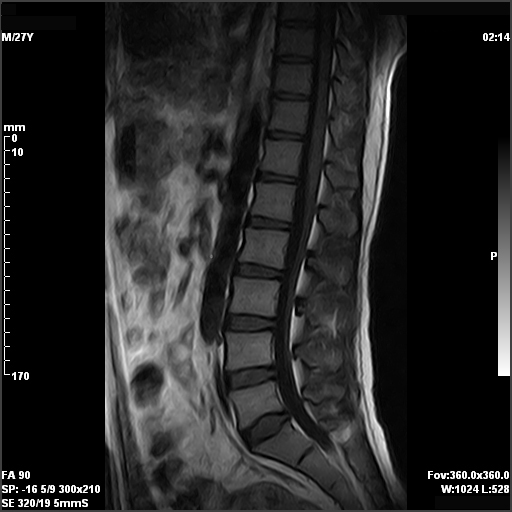

From health.ucdavis.edu

Brain and Spine MRI Spectrometer Mri Find out how mrs can help in the diagnosis of diseases of the brain and other parts of the body. Mr spectroscopic imaging (mrsi) has become a valuable tool for quantifying metabolic abnormalities in human brain, prostate, breast and other organs. Learn about mrs, a diagnostic imaging technique that measures the concentration of specific chemicals in tissues. Today mrsi allows. Spectrometer Mri.